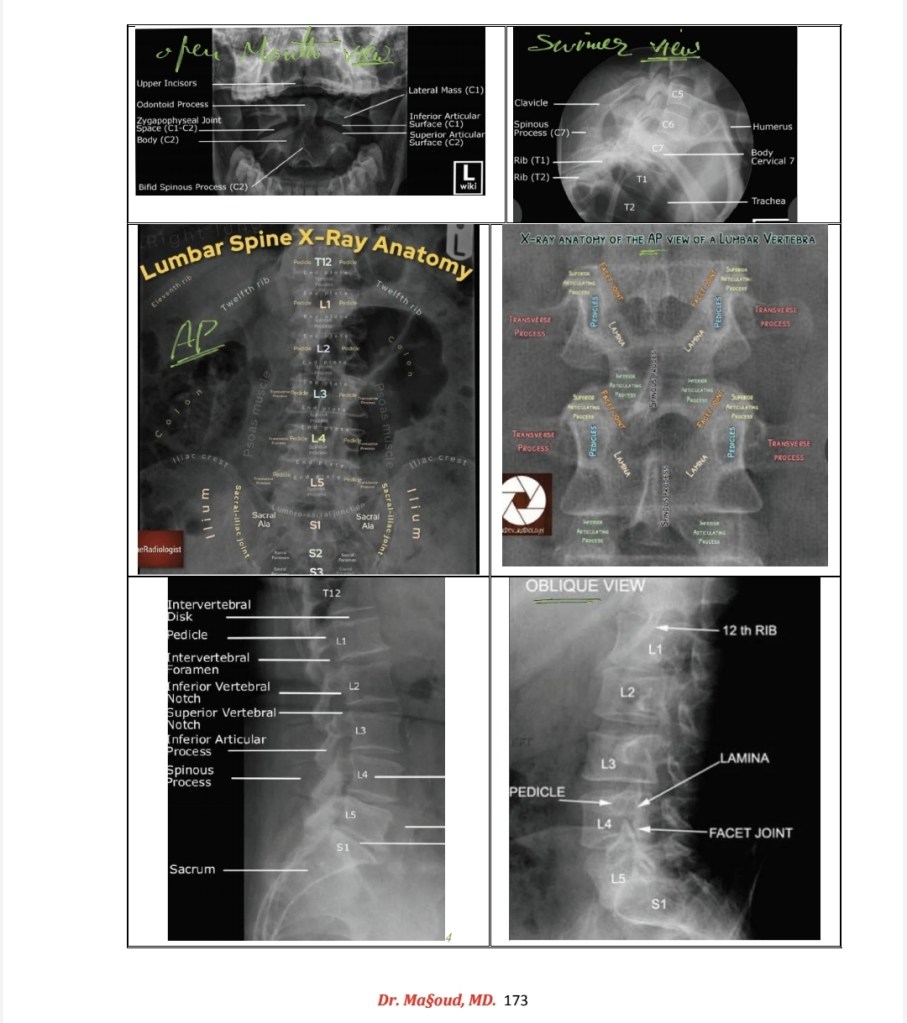

Spine imaging